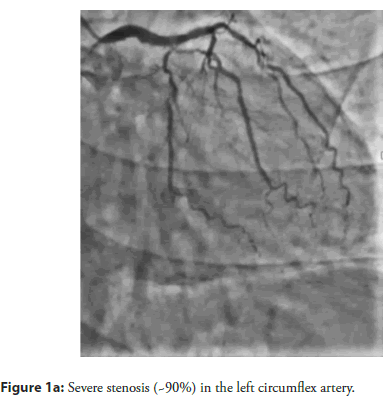

On admission, his blood pressure was 120/80 mmHg, and his heart rate was 72 beats per minute. Electrocardiography (ECG) demonstrated nonspecific ST-T wave changes in leads I, II, III, aVF, and aVL. Laboratory evaluation showed normal cardiac enzyme levels. Transthoracic Echocardiography (TTE) revealed a Left Ventricular Ejection Fraction (LVEF) of 62% without regional wall motion abnormalities. Diagnostic Coronary Angiography (CAG) demonstrated 90% stenosis in the Left Circumflex Artery (LCX) and Obtuse Marginal Branch 2 (OM2), along with total occlusion of the proximal Left Anterior Descending (LAD) artery (Figure 1a–Figure 1c).

Figure 1a: Severe stenosis (~90%) in the left circumflex artery.